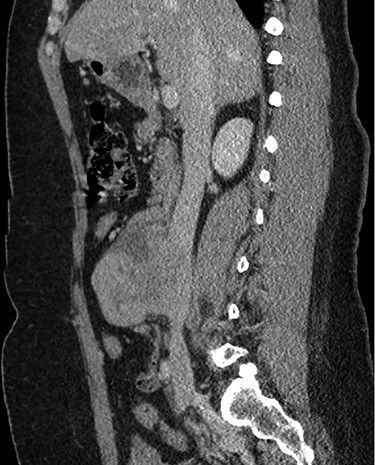

Abdominal CT demonstrating the length and location of the IVC in relation to the aorta.

The patient had a body mass index of 40, so combined with her presentation, age and gender. The presumptive diagnosis was of gallbladder pathology, which prompted an abdominal ultrasound. Ultrasound revealed a large 7.7 × 6.3 × 7.2 cm heterogenous, hypoechoic masslike lesion overlying the IVC (Fig 1). Abdominal CT was performed, which revealed an 8.9 × 7.9 × 9 cm multilobulated, heterogeneous soft tissue mass in the right hemiabdomen, encasing the IVC and partially encasing the distal abdominal aorta (Figs. 2–4). CT-guided biopsy was performed, which revealed an LMS.

A midline exploratory laparotomy was performed. The tumor extended from inferior to the renal veins to superiorly of the bifurcation. The tumor abutted and partially encased the aorta but did not invade it. Once the tumor was fully mobilized, the patient was heparinized and the vena cava was proximally and distally clamped (Fig 5). The vena cava and tumor were removed en bloc and sent to histopathology. A 22 mm Gelweave Dacron graft was inserted using 5–0 Prolene both proximally and distally (Fig 6). Clamps were removed, and hemostasis was achieved with an overall estimated blood loss of 50 ml. Histopathology of the specimen confirmed an LMS with clear surgical margins.